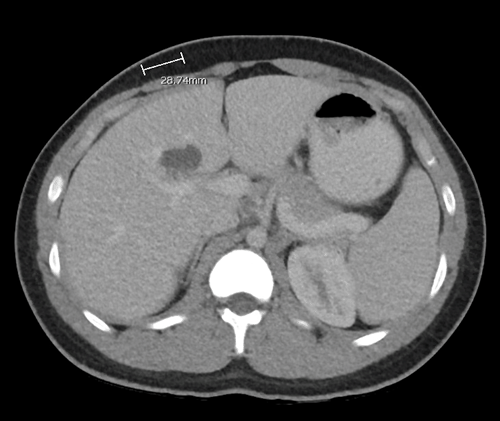

There did not appear to be an obvious choledochal cyst in the field of dissection after mobilization of the gallbladder and hepatoduodenal ligament. An intraoperative cholangiogram was performed, which demonstrated an intrahepatic saccular cyst originating off of the right hepatic duct, with one communicating biliary connection (Figure 3). The cyst appeared to be an intrahepatic type II choledochal cyst. The intrahepatic cyst was dissected away from the liver parenchyma and entered. Sludge and stones were removed, and then the feeding duct off the right hepatic duct was clamped, confirming exclusion of the cyst. The feeding duct was then clipped to exclude the cyst permanently. Complete excision of the cyst was attempted, but the proximity of the right hepatic duct precluded completion of the excision. Mucosectomy was performed except for the portion intimately adhered to the right hepatic duct; the remaining portion of the cyst was fenestrated and fulgurated. A confirmation cholangiogram demonstrated complete exclusion of the cyst and intact biliary tree anatomy (Figure 4).

Figure 3. Intraoperative Cholangiogram Demonstrating Choledochal Cyst Originating Off Right Hepatic Duct. Published with Permission

CBD = common bile duct, CHD = common hepatic duct, CDC = choledochal cyst. Arrow points to right hepatic duct and left hepatic duct bifurcation.